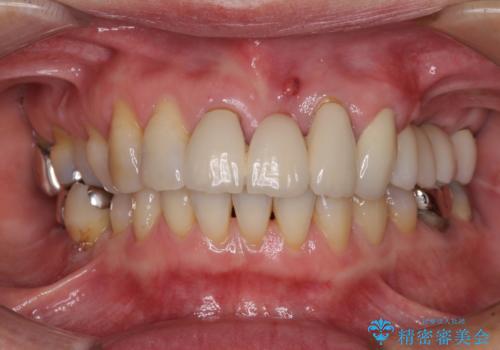

インプラントを埋入するために必要な骨の高さがなかったため、上顎洞底の粘膜を挙上しました。

手術後は処置部に痣や腫脹が出現したり、痛みが出たりしましたが、補綴治療後は咬み合わせが安定し、大変満足していただきました。